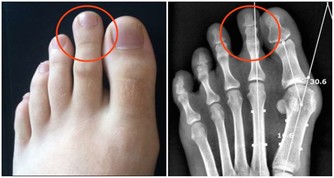

② 胃潰瘍。酗酒還會嚴重刺激胃部,容易造成胃出血,威脅生命安全。